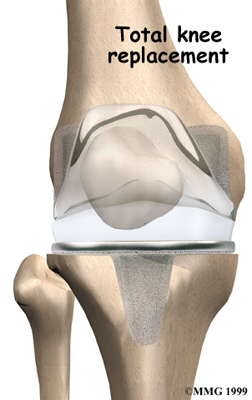

Artificial Knee Replacement

An artificial knee replacement is the ultimate solution for advanced knee OA.

Surgeons prefer not to put a new knee joint in patients younger than 60. This is because younger patients are generally more active and might put too much stress on the joint, causing it to loosen or even crack. A revision surgery to replace a damaged prosthesis is harder to do, has more possible complications, and is usually less successful than a first-time joint replacement surgery.

Related Document: FYZICAL Brodie Lane's Guide to Artificial Joint Replacement of the Knee